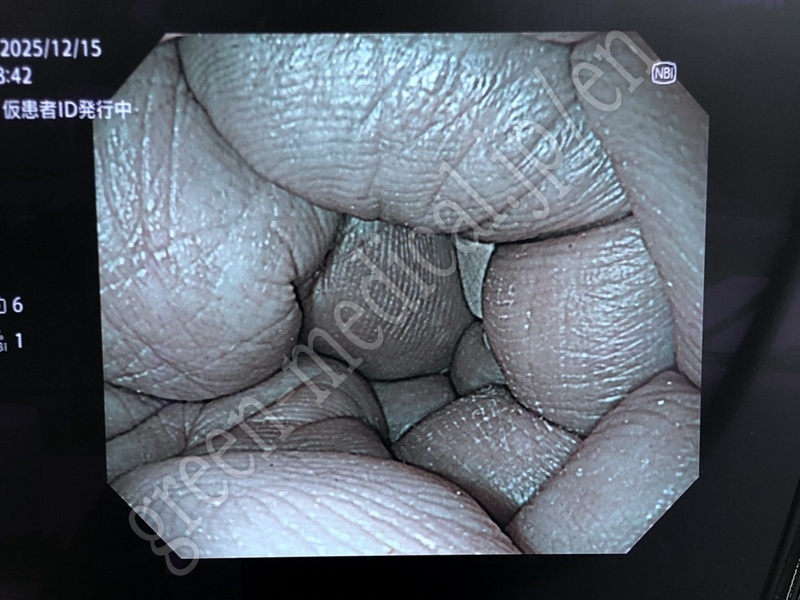

Video System Center EVIS X1 CV-1500

Fabricante

OLYMPUS

Tipo

EVIS X1 CV-1500

Inventario

115707